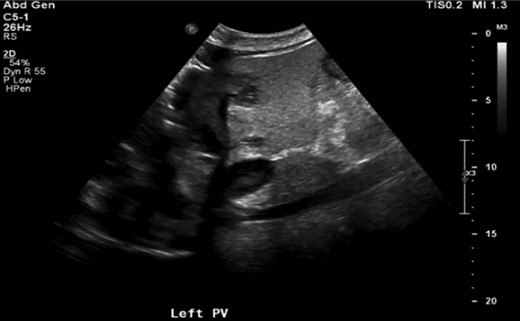

Abdominal imaging findings: axial computed tomography (CT) scan showing the intrahepatic dilation of the left sided biliary system (arrow) from cranial (A) to caudal (B), diffusely thickened gallbladder wall (C, arrow) and left intrahepatic abscess (D, arrow).

Repeat CT imaging revealed continued thrombosis of the left portal vein and anterior branches of the right portal vein and right hepatic artery (Fig. 3). Due to persistent left intrahepatic abscess and concern for an underlying obstructive process in the left biliary system, the patient underwent an endoscopic retrograde cholangiopancreatography (ERCP) which revealed choledocholithiasis which was removed followed by sphincterotomy and stent placement. He subsequently underwent a spyglass™ procedure which noted a left biliary tract occlusion secondary to a mass which was biopsied. Pathology, however, was noted to be benign with debris and bile crystalline material and rare fragments of fibrous tissue with biliary-type epithelium.

Axial CT scan showing thrombosis of the left portal vein (arrow).